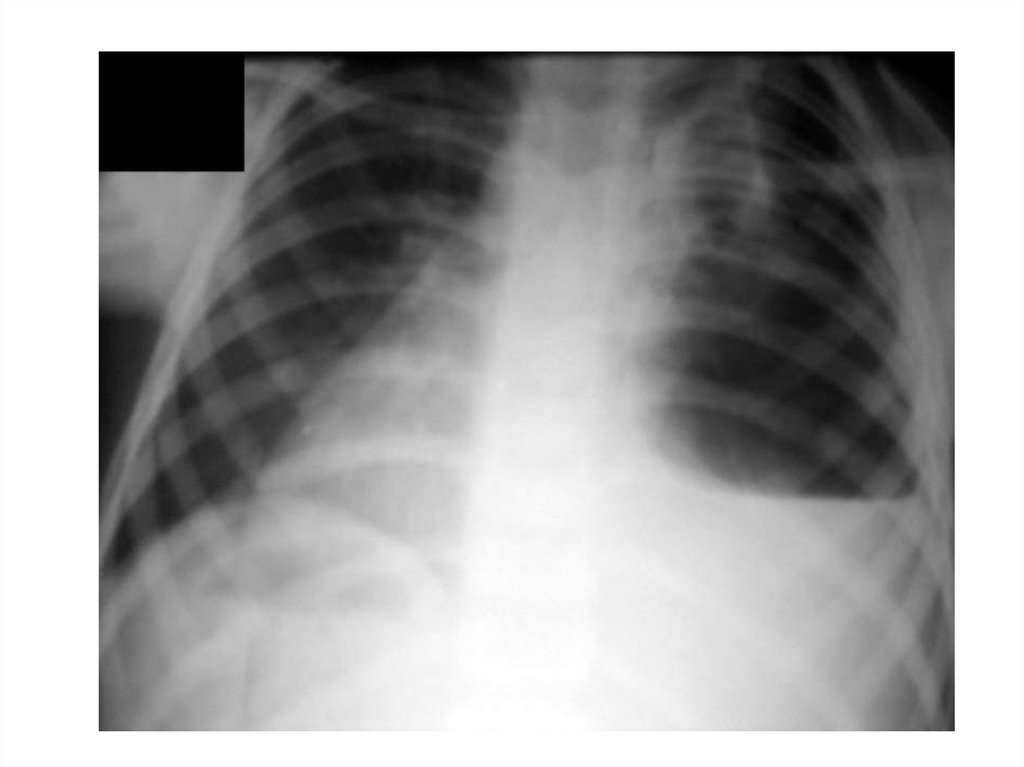

• Среди рентгенологических признаков

повреждений пищевода следует различать

косвенные признаки и прямые.

• Косвенные признаки можно определить при

полипозиционной рентгеноскопии шеи и грудной

клетки, выявленные изменения фиксируются затем

на рентгенограммах. Наиболее распространенным

признаком повреждения пищевода является

наличие эмфиземы околопищеводной

клетчатки шеи и средостения, межфасциальных

пространств шеи, подкожной клетчатки.

Возникновение пневмоторакса,

гидроторакса или гидропневмоторакса также

является косвенными признаками разрыва

пищевода.